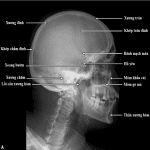

Giải Phẫu X-Quang Sọ Mặt | Bài giảng CĐHA

Giải phẫu X-quang xương hộp sọ – xương hàm mặt…